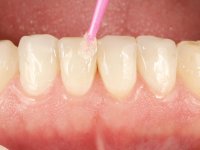

Realizado o diagnóstico e tomada a decisão quanto ao tratamento a executar, tornou-se importante definir qual a sequência de trabalho a adotar no sentido de conseguir a reabilitação da D.V.O. (V.D.O), de forma progressiva e equilibrada. Na primeira fase fez-se uma pré-impressão da arcada inferior com silicone tipo “putty” e em seguida realizou-se o preparo dentário de todo o sector posterior. O preparo para os overlays foi feito coronalmente à linha amelo cementaria no sentido de ser o mais conservador possível. A impressão foi feita com técnica de dupla mistura após afastamento gengival realizado com pasta de caulino. A provisória foi realizada com resina composta de polimerização dual. Em laboratório foram realizados os overlays após se ter aberto ligeiramente (1,5mm) a D.V.O. nos modelos montados em articulador semi-ajustável. Simultaneamente o sector antero-inferior foi encerado no sentido de acompanhar este aumento da D.V.O. Também foi confecionada uma chave de silicone translucido para posterior confeção dos provisórios antero-inferiores. Em boca foi primeiro realizada a provisionalização dos dentes anteriores utilizando resina composta previamente aquecida após preparação das superfícies dentárias para a adesão. Foi colocado o dique de borracha para promover o isolamento absoluto e posteriormente foram colados os overlays. Em laboratório foi realizada nova chave de silicone para confecionar os provisórios antero-superiores. Seguidamente em boca foram preparados os seis dentes antero-superiores após colocação do fio de afastamento gengival. Feita a preparação adequada das superfícies dentárias foi realizada a impressão com técnica de dupla mistura e a respetiva provisória. Em laboratório foram confecionadas 6 facetas feldespáticas num modelo de trabalho tipo “Geller”. A provisória foi removida e as facetas foram coladas em boca utilizando um isolamento relativo competente. Esta opção foi tomada em virtude de uma prévia experiencia negativa com a colocação do dique de borracha na mandibula. Após a colagem dos laminados antero-superiores foram dadas 12 semanas para avaliar a adaptação do paciente à nova situação e então iniciar a confeção das facetas antero-inferiores. Após colocação do fio de afastamento gengival. foram feitos os preparos dentários adequados e em seguida foi feita a impressão. Também foi feita a preparação do dente 3.4 que, entretanto, tinha sofrido uma fratura do overlay. As facetas e a restauração do 3.4 foram realizadas num modelo de trabalho tipo “Geller”. Após remoção da provisória, as facetas foram coladas em boca, utilizando um isolamento relativo pelas razões apontadas anteriormente. Após colocação do trabalho o paciente foi reabilitado por outros colegas com um implante na zona do 2.6 e substituição da coroa aparafusada sobre o implante colocado no local do 3.5. Posteriormente surgiram fraturas nos overlays dos dentes 4.7 e 3.7 que foram reabilitados com overlays em Zr.